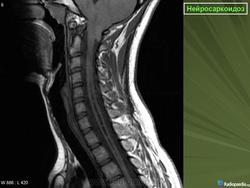

Случай 5: вовлечение спинного мозга

Рисунок 8

Рисунок 8 Нейросаркоидоз.